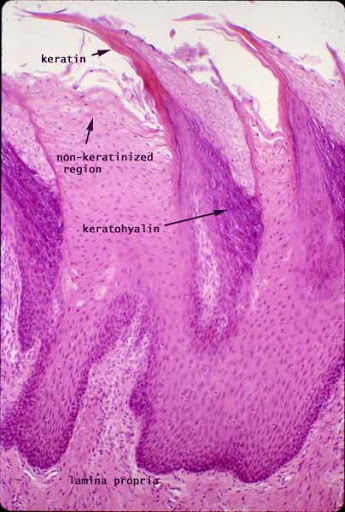

1. What type of tissue consists of 4 layers and is especially found in the skin?

Explanation

Keratinised stratified squamous epithelium is a type of tissue that is tough and waterproof, making it ideal for protecting the underlying layers from abrasions and water loss. It is commonly found in the epidermis of the skin.

7. What type of epithelium is characterized by being non-keratinised and stratified with three layers?

The question asks for the specific type of epithelium that fits the description of being non-keratinised, stratified, and composed of three layers. The correct answer, non-keratinised stratified squamous epithelium, matches these criteria perfectly, making it the right choice. The other three options do not align with the given characteristics, hence they are incorrect.